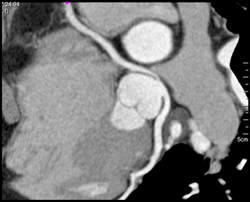

Anomalous RCA Off Lca